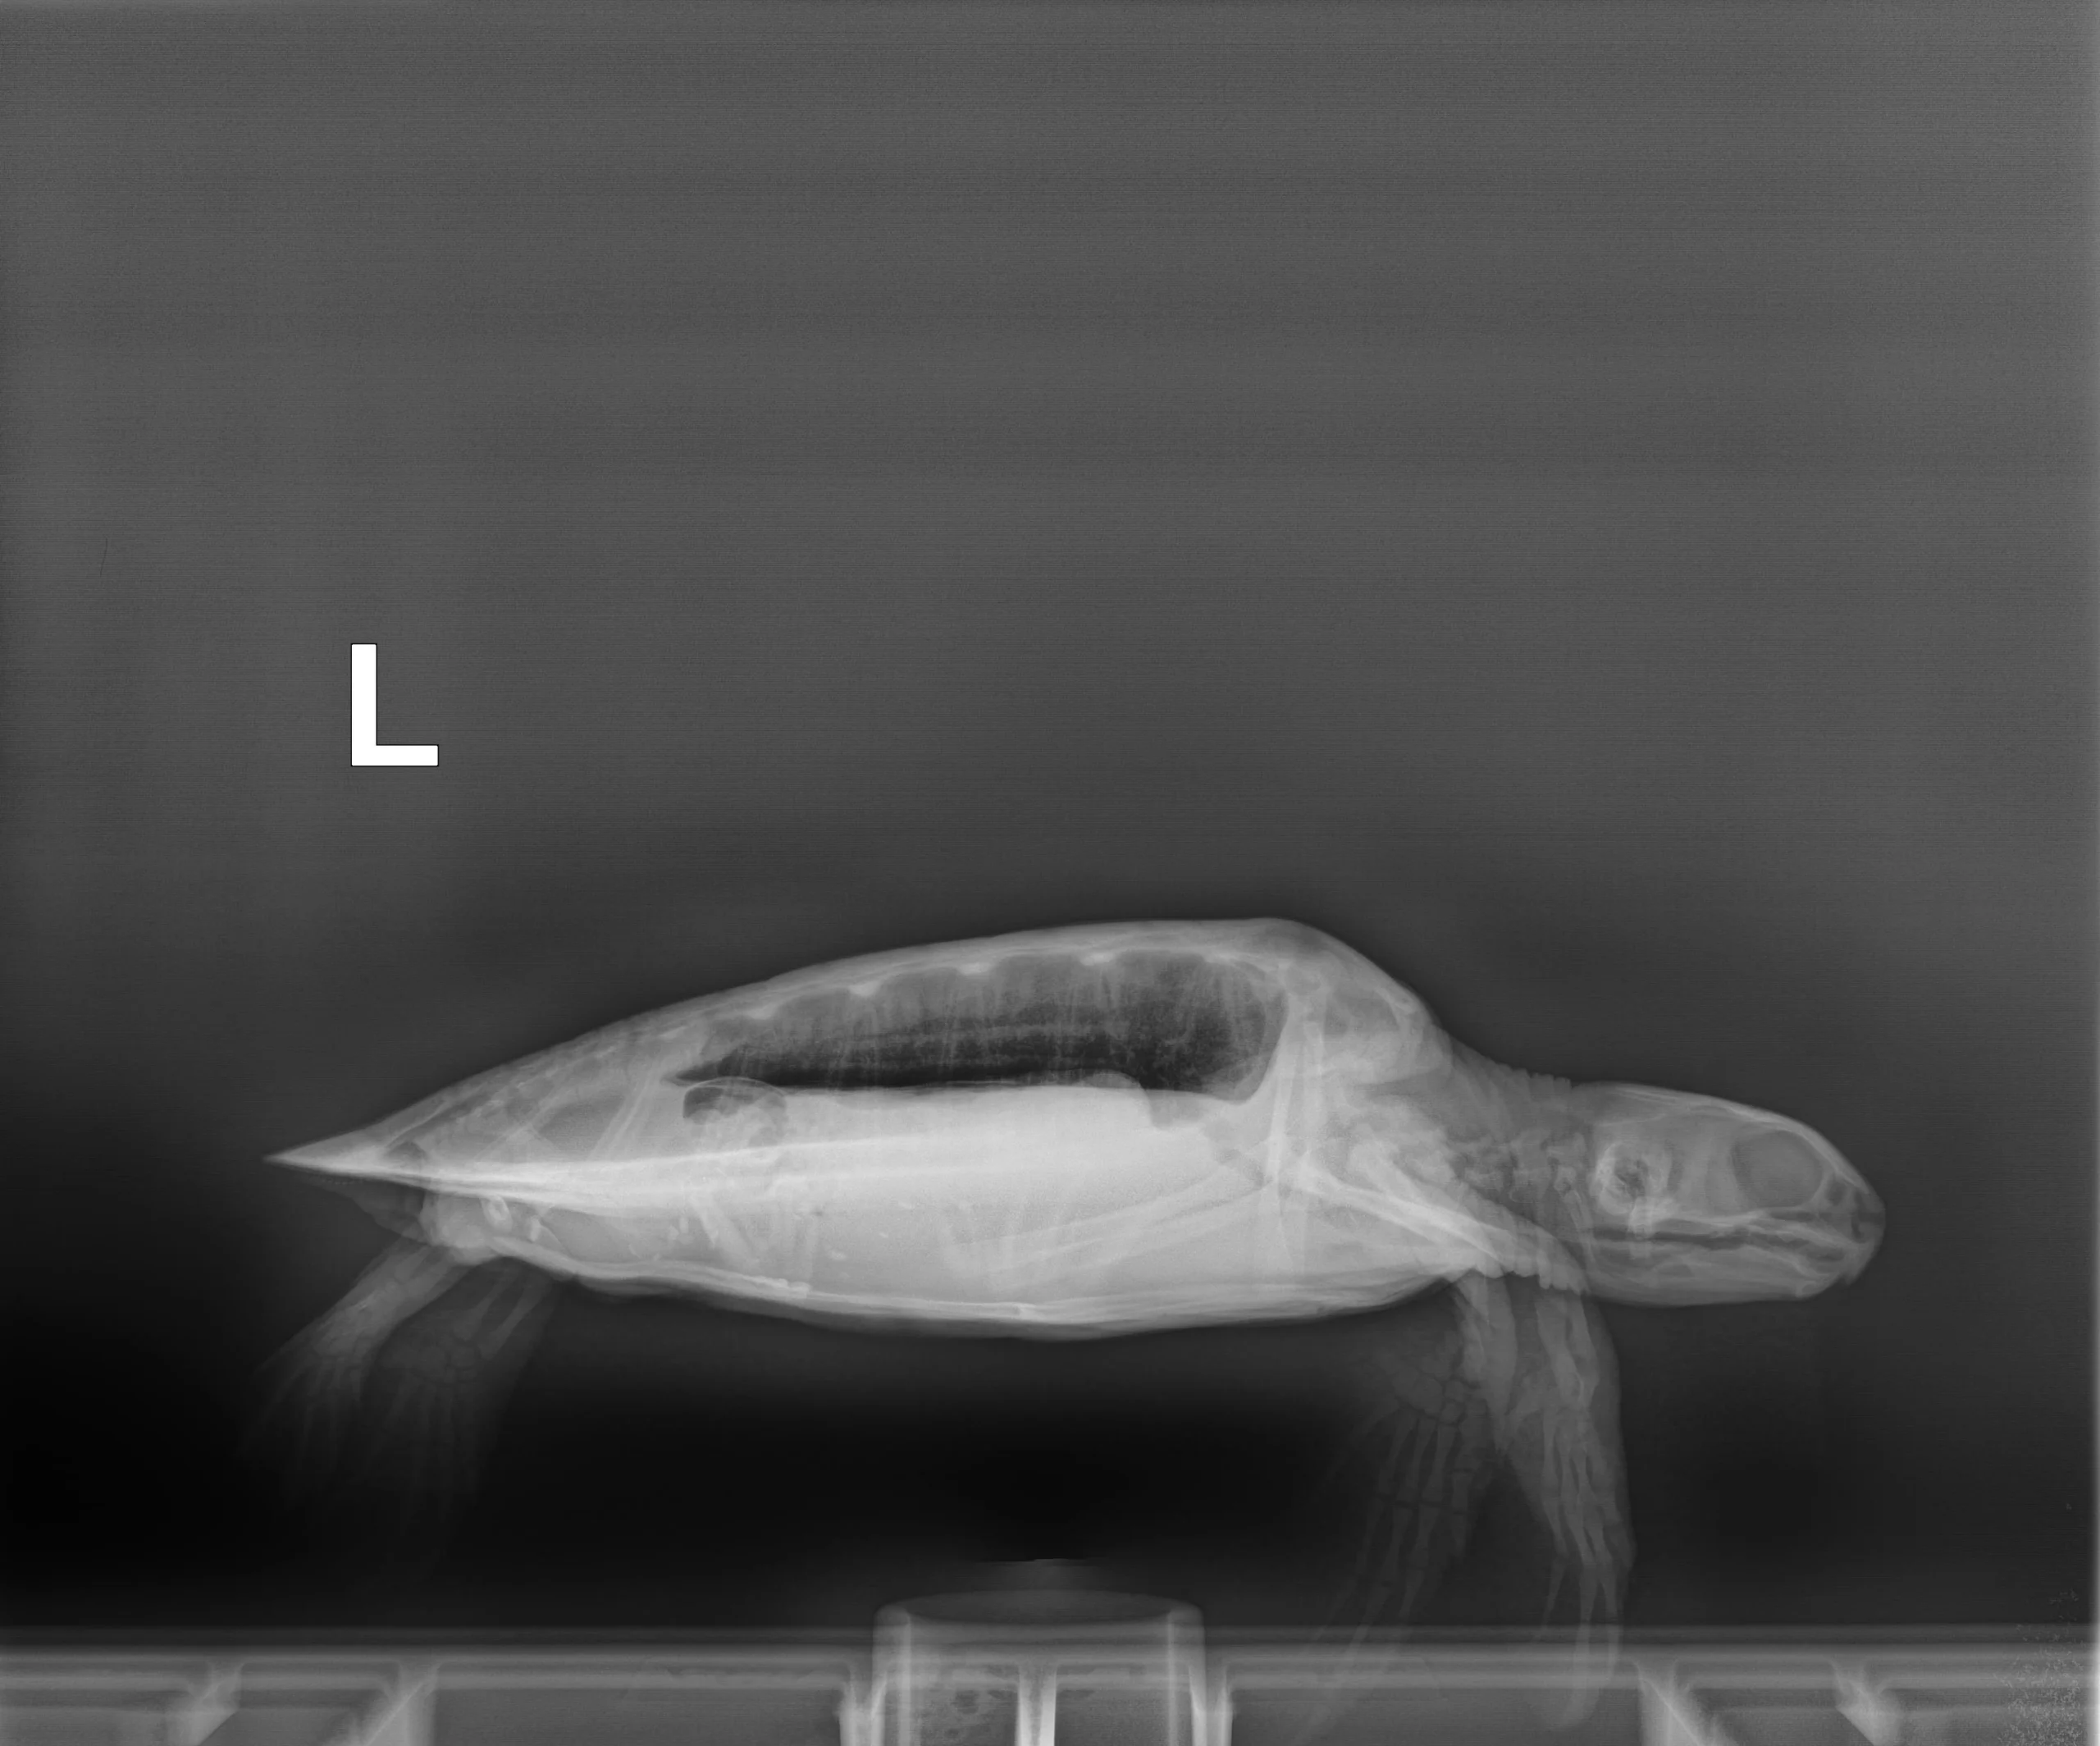

1.30 kg juvenile Atlantic Green sea turtle

Plastron: Minor abrasions

External Wounds: hook wound in front right shoulder area ventral side

Head/Flippers/Soft Tissue: One small notch out of the right front flipper, small abrasion on the rear left flipper, small cut around nail of right rear flipper